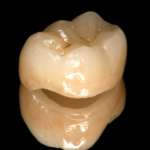

La ricostruzione anatomica della cresta marginale nei restauri di classe II Premium

La CBT, descritta in questo aggiornamento, è una tecnica ricostruttiva

che consente la conversione di una cavità di classe II in classe I, con il...